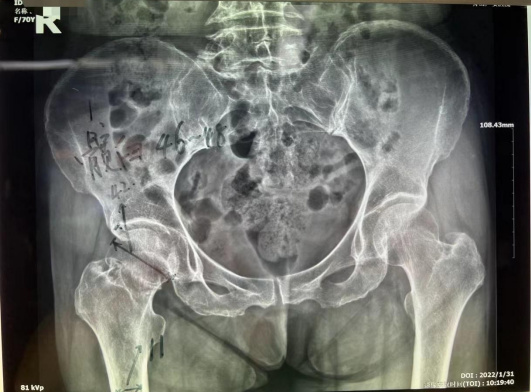

家住普陀的鄭阿姨今年70歲,大年初一在路上行走時不慎被電動車撞倒,右髖部當即動彈不得。當即被家人送來我院就診。門診拍片診斷為右股骨頸骨折,由于保守治療導致股骨頭壞死、骨折端不能生長的可能性極大。而且長期臥床也容易引發(fā)褥瘡、深靜脈血栓、肺部感染等并發(fā)癥。醫(yī)生建議其行全髖關節(jié)置換術。

患者為右股骨頸骨折